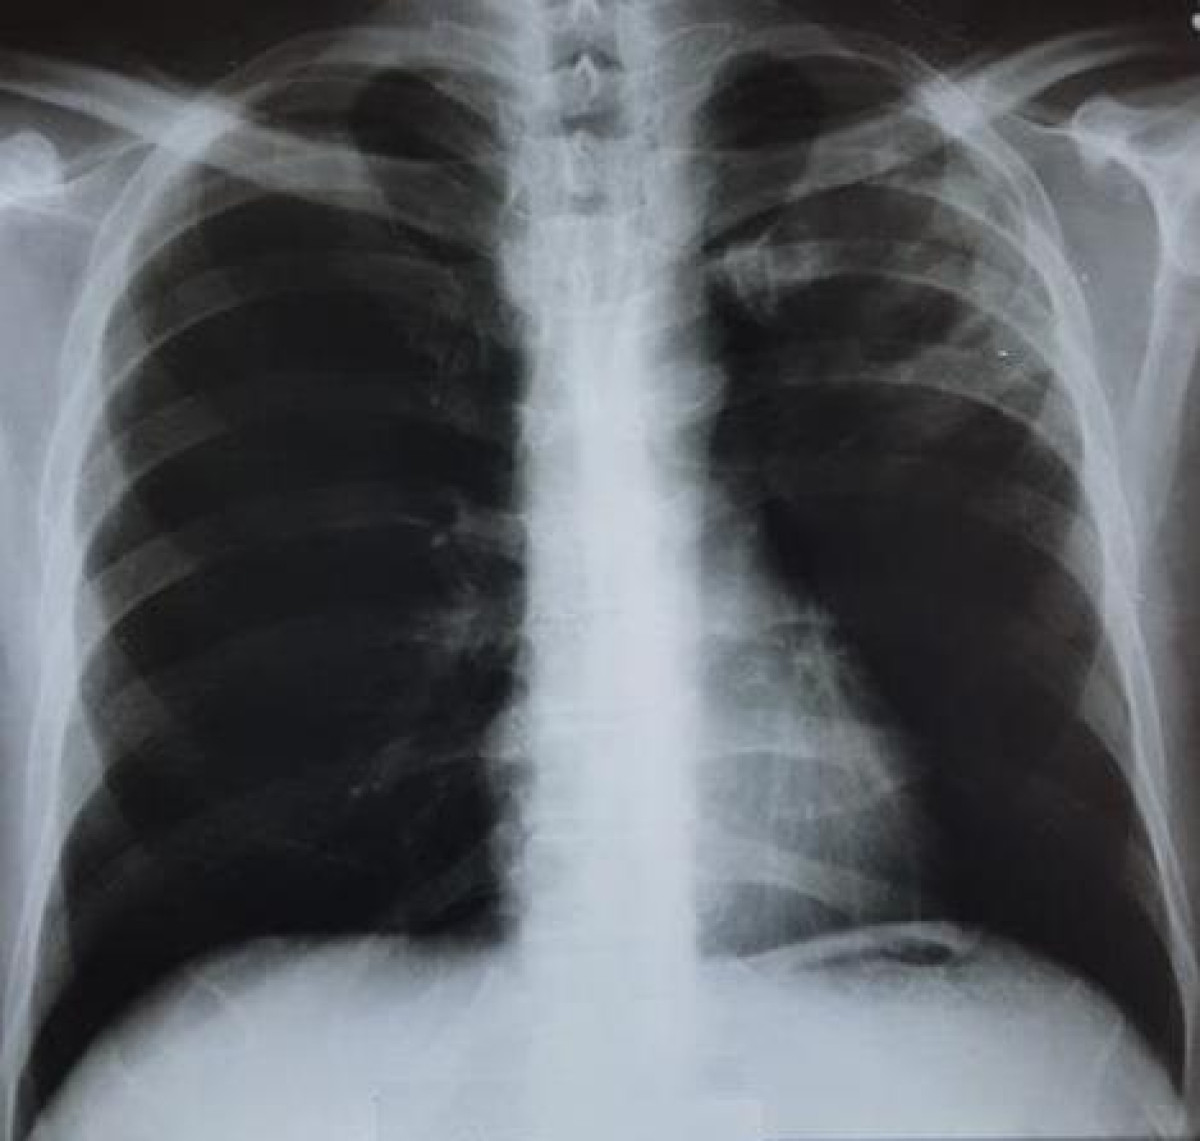

Бишкек шаарындагы №37 мектептин математика мугалиминен кургак учуктун ачык түрү аныкталды. Бул тууралуу окуучулардын ата-энелери 24.kg агенттигине кабарлаган.